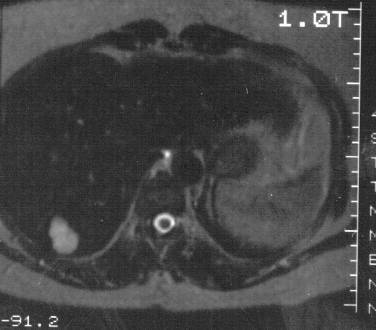

Concerning the HCC, the knowledge of history is very important for the decision and usually the oncoteams consider the performance of an imaging modality guided biopsy basically important for the further therapeutic decisions (because of the hystological validation rather core biopsy should be performed! (Figure 26, 27, 28).

Figure 26: HCC, verified with FNAB, US

Figure 27: HCC, TAE, agniography

Figure 28: HCC, native CT after TAE